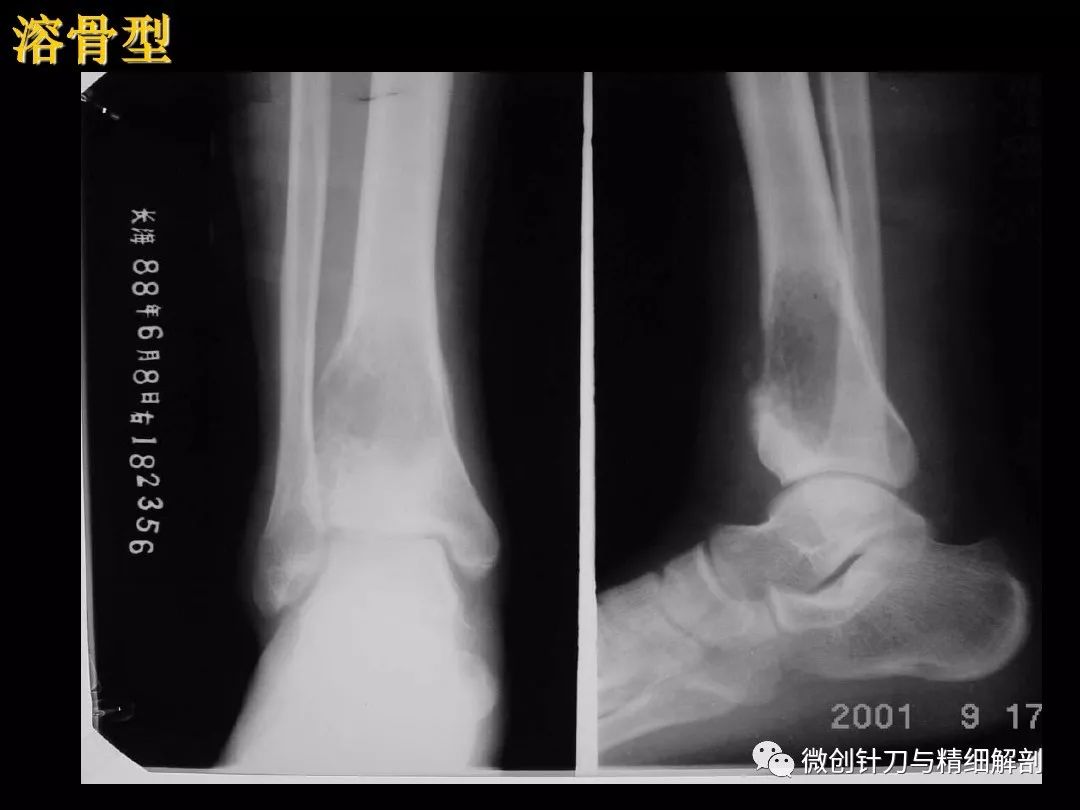

医学影像-骨与关节

踝关节骨折病例